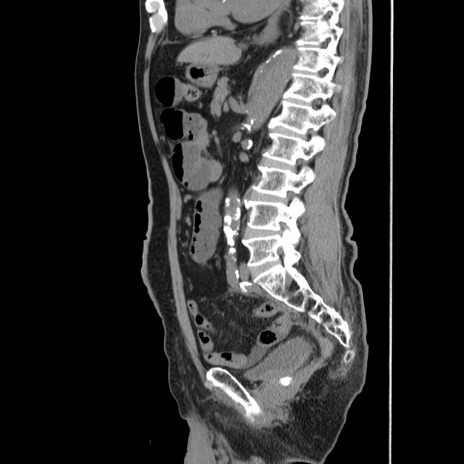

症例24(矢状断像)

【症例】80歳代男性

【主訴】左側腹部痛、嘔吐

【現病歴】本日早朝より左腹部に痛みあり。昼頃嘔吐認めたため、救急要請。

【既往歴】直腸癌(Mile手術)、胆摘

【身体所見】意識清明、BT 35.9℃、BP 221/93mmHg、SpO2 97%(RA) 、腹部:左ストーマ周囲に限局性の腹部膨隆あり。 膨隆部自発痛・圧痛あり・軟。

【データ】WBC 7700、CRP 0.09